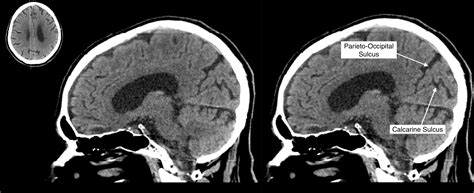

The anatomy of the human brain highlighting the Parieto Occipital Sulcus

The Parieto Occipital Sulcus is not only a random fold in the brain; it is a significant anatomical watershed that is easily identifiable on a sagittal cross-section. It commence near the top of the hemisphere, extending down and forward until it meets the calcarine sulcus, make a articulation that is vital for visual pallium orientation. This sulcus efficaciously maps out the borderline between two of the four major lobes of the brain.

• Medial Surface: It is prominently seeable on the median surface, meaning it can be best realise when the brain is catch from the midline between the two hemispheres.

• Lobular Boundary: It marks the posterior bounds of the parietal lobe and the prior limit of the occipital lobe.

• Relationship with Other Fissure: It function as a connection and boundary point for the precuneus, which consist in front of it, and the wedge, which dwell behind it.